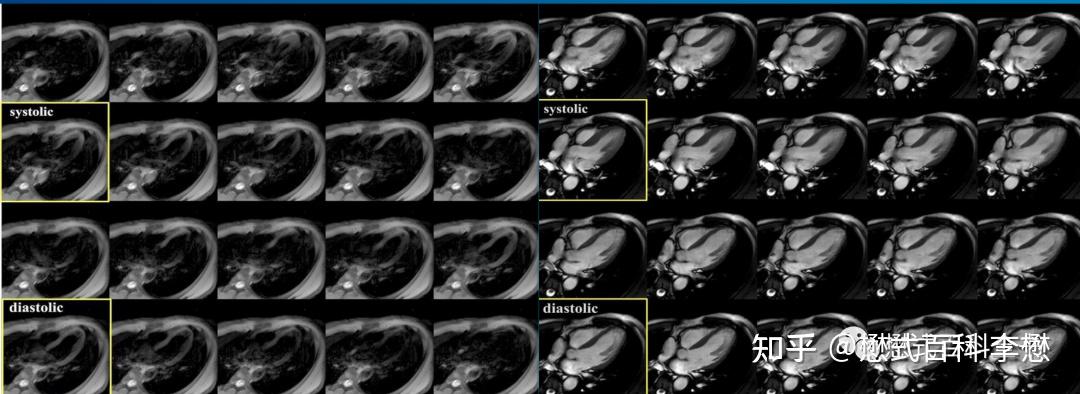

重聚回波SSFP序列 - 知乎